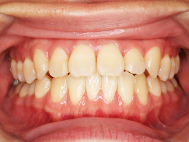

After

左上の前歯内側に入っている下の前歯ガチャ歯

左上前歯が下の歯の内側に入っているのが気になるとの事で来院されました。目立たない矯正治療を希望しているとのこでした。 上顎の装置は、歯の裏側(リンガル装置)で下顎は表側で矯正治療を行いました。口を閉じた時、上の前歯が内側に入っている為に下の歯を前に押し出している状態でした。その為、上の歯を前に出すだけではその歯が下とのかみ合わせの関係で、前に飛び出すような治療となってしまいます。 今回の症例ではシュミレーションを見て頂き、下の歯も治療し、内側へ下げることによって上の歯も飛びだすことなく、キレイにおさまることを説明し、上下一緒に矯正することをお勧めさせて頂きました。